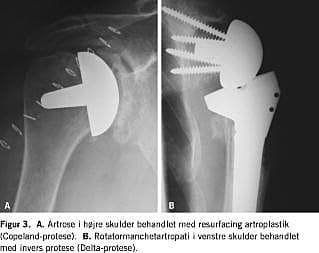

Hos patienter med artrose eller artrit, hvor der er god knoglekvalitet af caput humeri, kan man anvende en såkaldt resurfacing -artroplastik, hvor afskæringen af caput humeri er minimal. En væsentlig fordel ved denne protese er, at en evt. senere revision lettes på grund af det næsten intakte caput humeri (Figur 3A ).

Endelig kan man i tilfælde af manglende rotatormanchet anvende en speciel »omvendt« (invers) skulderprotese (Delta-protese). Ved anvendelse af denne protese flyttes skulderens omdrejningspunkt mere medialt, således at m. deltoidea kan kompensere for den manglende rotatormanchet ved abduktion. På grund af protesens udformning er der også nedsat risiko for proksimal migration af protesen. Det er en forudsætning for anvendelse af denne protese, at knoglekvaliteten er god, specielt i cavitas glenoidales (Figur 3B ).

Der foreligger ligeledes kun få opgørelser af resultaterne efter resurfacing -artroplastik. Levy & Copeland [22] fandt god smertelindring og et godt funktionelt resultat hos op mod 90% af 103 patienter fulgt i gennemsnitlig 6,8 år. Tilsvarende resultater blev fundet af Ålund et al [23].